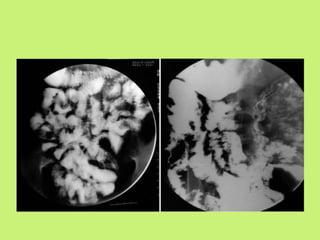

Barium studies

• It has been documented that barium studies are

useful in 75% patients with suspected intestinal

tuberculosis.

• Different barium studies are used to diagnosis at

the basis of involved site.

Barium swallow

Barium meal follow through

Barium enema

Ba meal follow through

• Best diagnostic test for intestinal lesions.

• In Ba studies features may be seen :

1. Accelerated intestinal transit.

2. Hyper-segmentation of Ba column(chicken

intestine)

3. Luminal stenosis with smooth but stiff

contours(hourglass stenosis)

4. Multiple strictures with segmental dilatation of

bowel loops and matted.

Findings of barium meal follow

through study in intestinal TB

Group I Highly suggestive of intestinal tuberculosis if one or

more of the following features are present.

• Deformed ileocaecal valve with dilated ileum

• Contracted caecum with abnormal ileocaecal valve or terminal ileum.

• Stricture of ascending colon with shortening or

involvement of ileocaecal region.

Group II Suggestive of intestinal tuberculosis if one of the

following is present:

• Contracted caecum

• Ulceration or narrowing of terminal ileum

• Stricture of ascending colon

• Multiple sites of narrowing and dilatation leading to

formation of small bowel loops.

Group III Non-specific changes

Features of adhesions, dilatation and mucosal thickening of small bowel loops

Group IV Normal study